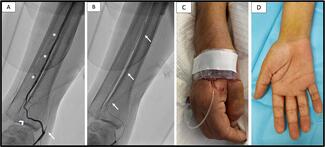

A 59-year-old diabetic man with a history of numerous coronary angiographies (CAs) and peripheral artery disease underwent CA due to a non-ST elevation myocardial infarction. Femoral, radial, and ulnar arteries were unpalpable.